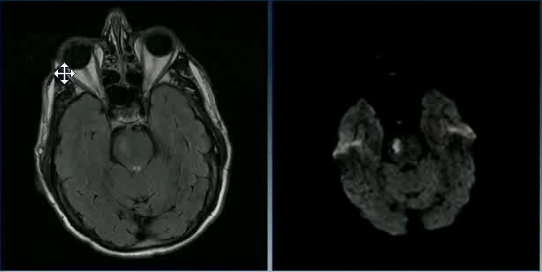

A 20 year old man tries to commit suicide by hanging himself. He is cut down after several minutes and is pulseless. He is resuscitated and regains a heartbeat and respiratory drive and cough to suctioning. Three days later, his exam has not changed. His MRI is attached.

What is the etiology of his brain injury?

Global hypoxia due to asphyxiation and compression of all four major vessels to the brain.

What areas or layers of the cerebrum are affected?

Lamina 3-5 of the entire cerebrum. These lamina are particularly sensitive to hypoxia and die earlier than other areas of the brain.

Case 2 Q# 3 of 4

Why are the ventricles and sulci barely visible in the MRI?

The ventricles and sulci have been compressed by widespread cortical edema

Case 2 Q# 4 of 4

When must this MRI have been taken? Why?

The MRI must have been taken a few days after the injury; cortical edema takes days to show up. Glial cells and astrocytes are able to survive longer (20-30min) during ischemia than neurons (6-10min); their (proportionately greater) survival kept most of the brain’s structure intact despite widespread neuronal death.